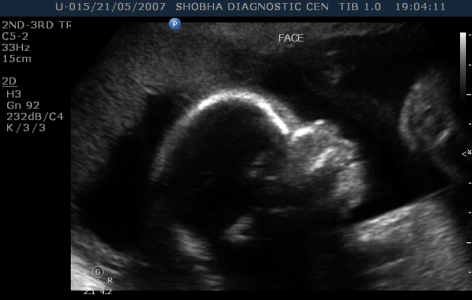

- Thorough scanning of your baby is done to know if baby is developing normally or not. Special attention is paid to brain, face, spine, heart, stomach, bowel, kidneys & limbs.